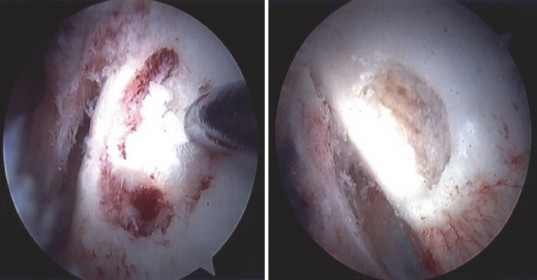

Locating the nidus is the most challenging aspect of the procedure. The overlying cortex may appear entirely normal, or it may exhibit subtle neovascularization, a localized hyperemic blush, or a slight cortical prominence.

The surgeon uses a combination of preoperative CT mapping, direct arthroscopic visualization, and intraoperative fluoroscopy to pinpoint the lesion. A spinal needle or a Kirschner wire is introduced percutaneously and advanced to the suspected location on the femoral neck. AP and lateral fluoroscopic views are obtained to confirm the trajectory and depth relative to the radiolucent nidus.

Once the location is confirmed, a high-speed arthroscopic burr is used to carefully unroof the overlying cortex. As the cortex is breached, the nidus typically appears as a distinct, hyperemic, cherry-red, granular tissue mass that contrasts sharply with the surrounding white, sclerotic bone.

Curettes and pituitary rongeurs are utilized to meticulously excavate the nidus. It is imperative to obtain adequate tissue samples for histopathological analysis to definitively confirm the diagnosis of osteoid osteoma and rule out malignancy or infection. Following the removal of the gross nidus, the high-speed burr is reintroduced to extend the resection margin by 1 to 2 millimeters into the surrounding reactive bone, ensuring complete eradication of the tumor and minimizing the risk of recurrence.